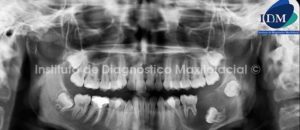

010 – Osteonecrosis

Paciente de sexo femenino y de 38 años de edad, es referida al Instituto de Diagnóstico Maxilofacial para la evaluación de un proceso infeccioso en el lado derecho del maxilar inferior.